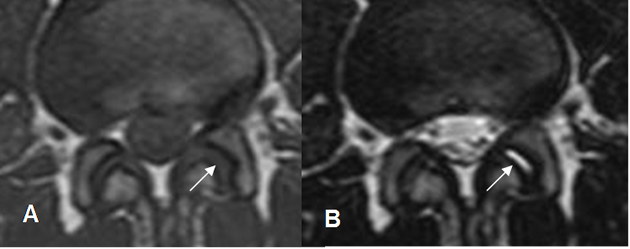

Fig 66. Articulaciones intervertebrales.

A: RM axial en T1 y B: RM axial en T2. Cambios degenerativos incipientes en la articulación interfacetaria izquierda, con presencia de líquido, hipointenso en T1 e hiperintenso en T2.